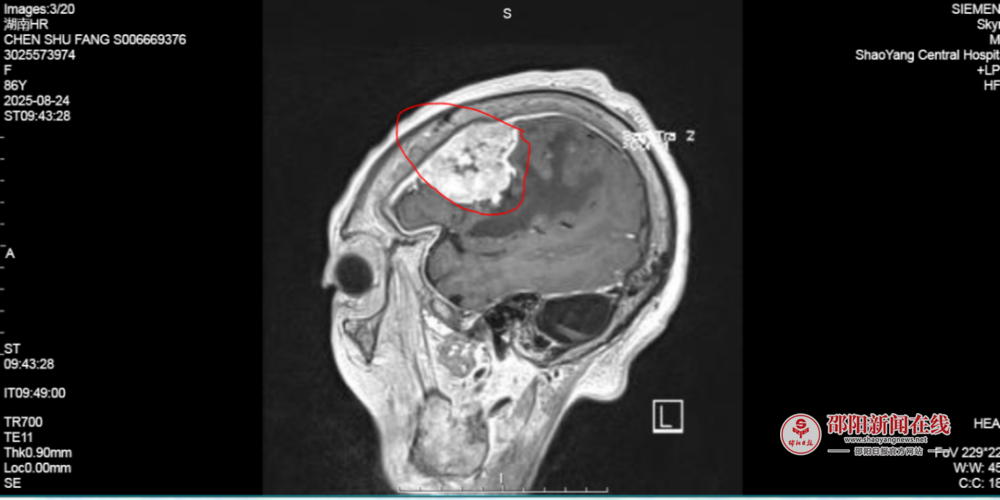

陈奶奶,86岁,因持续头痛、呕吐在家人的陪同下到该院就诊时,其颅内直径4cm的神经肿瘤已压迫脑功能区。出于对该院神经外科团队信任,陈奶奶及其儿女慕名找到蒋开源主任要求行开颅手术治疗。

8月27日,由蒋开源主任带领的神经肿瘤团队为陈奶奶进行开颅手术。手术进行顺利,颅内肿瘤完全切除。患者术后转至神经重症监护室,在一系列高精尖的预防性监护措施下,大大降低了并发症的发生率,提高了患者的治愈率。